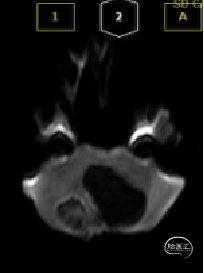

术前MRI